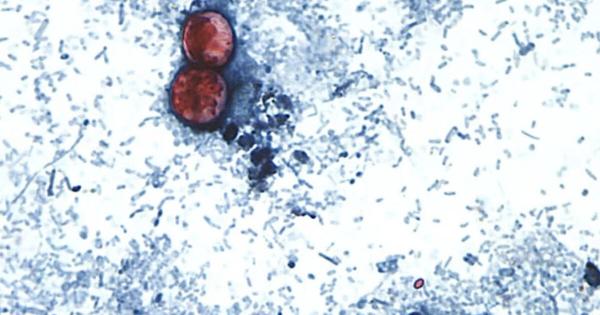

Πολύ σημαντικά οφέλη παρέχουν στην επιβίωση η ανοσοθεραπεία και οι στοχευμένες θεραπείες. «Πριν από το 2020, υπήρχαν πέντε σημαντικές μεταλλάξεις στα καρκινικά κύτταρα του πνεύμονα που αντιμετωπίζονταν με στοχευμένη θεραπεία. Σήμερα έχουμε εγκεκριμένες θεραπείες για εννέα μεταλλάξεις. Οι μεταλλάξεις αυτές καλύπτουν σχεδόν τα μισά αδενοκαρκινώματα του πνεύμονα», λέει η Dr. Xiuning Le, επίκουρη καθηγήτρια Ιατρικής Ογκολογίας στο πανεπιστήμιο.